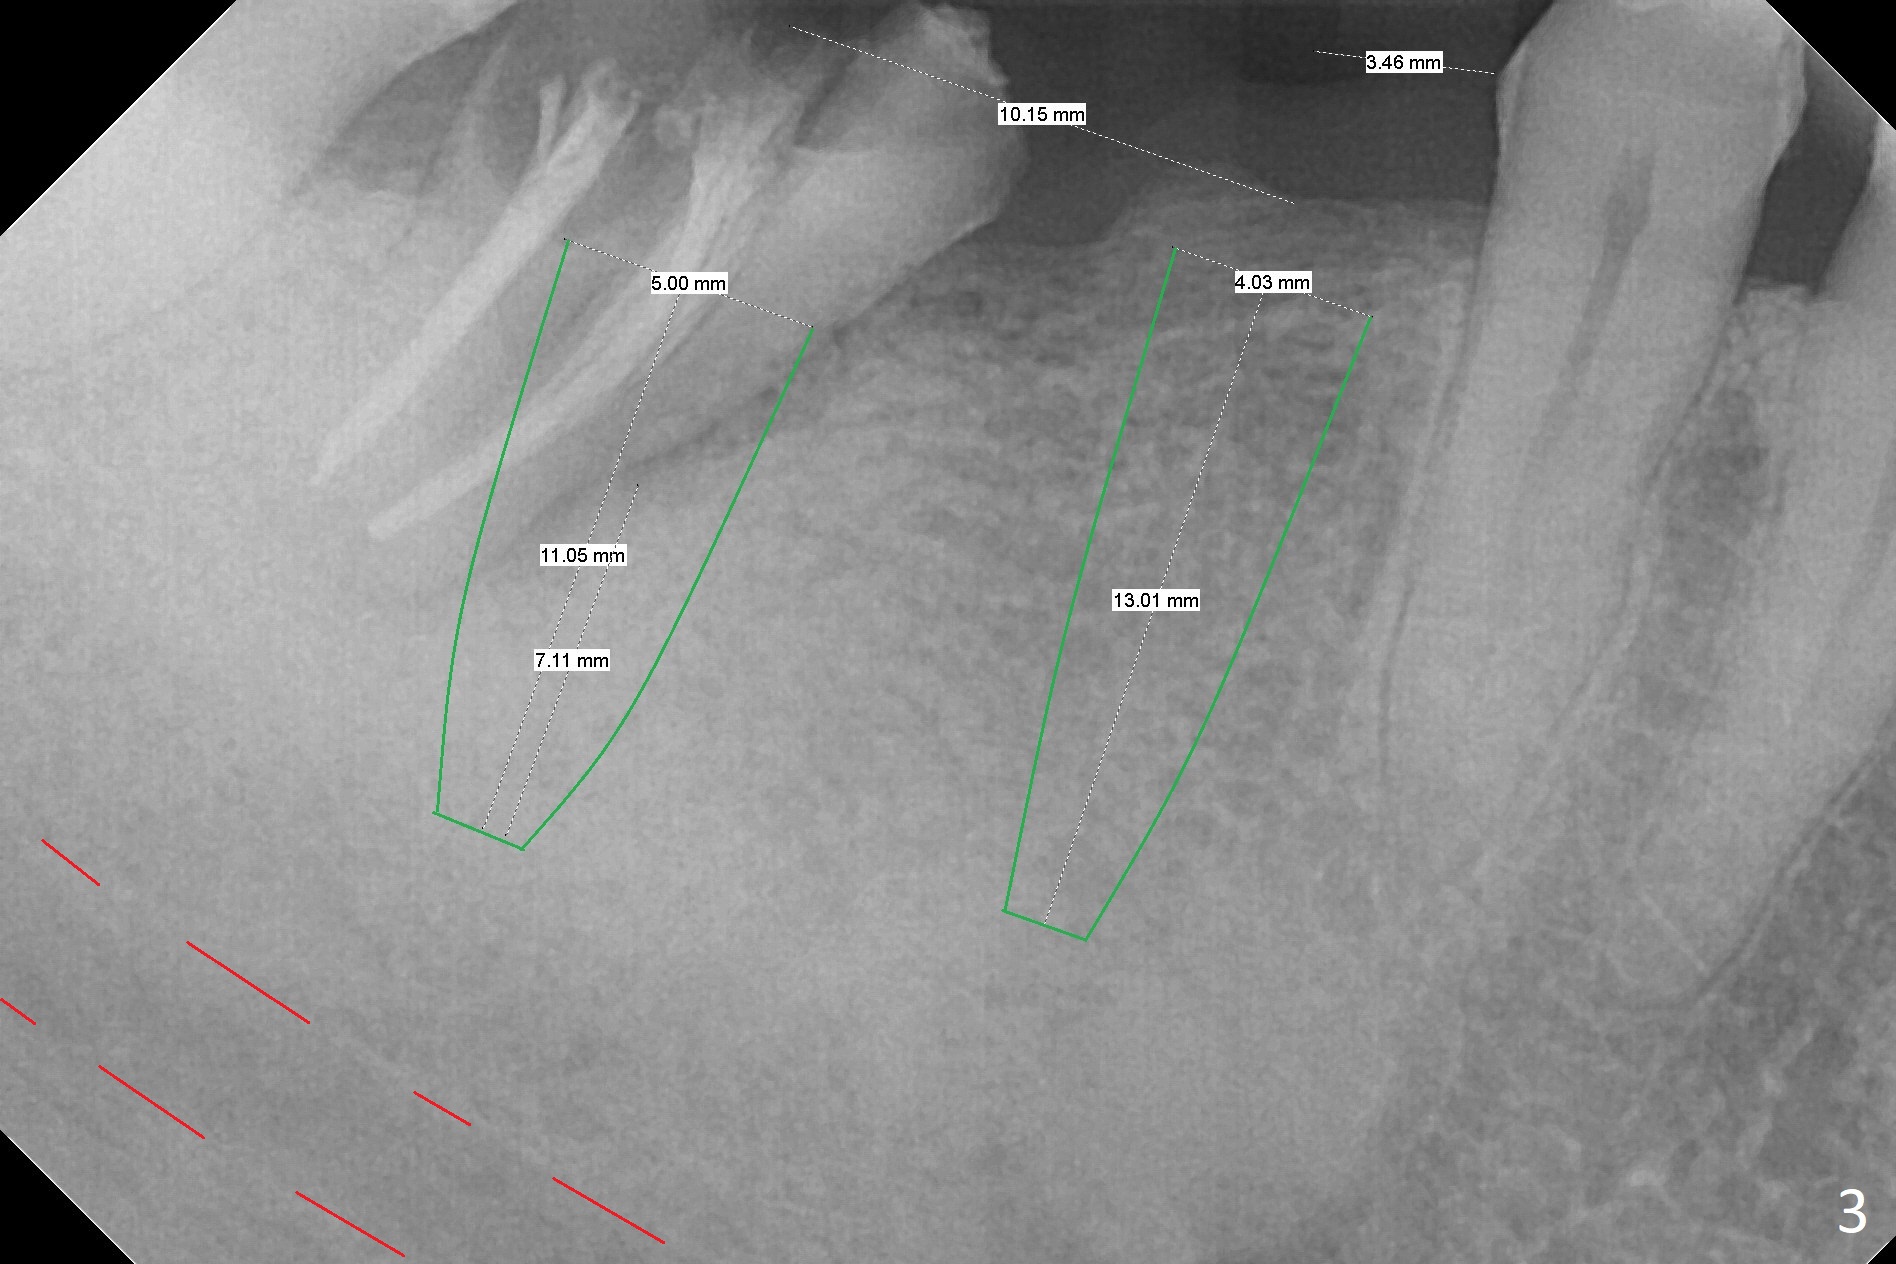

A 53-year-old woman has 2 lower failed FPDs with the right one dislodged (Fig.1,2). The pontic (#30) is as narrow as a premolar; prepare a 3.5 or 4.0 mm 2-piece implant (Fig.3). To gain more native bone for primary stability at #31, use Point Lindamann drill to initiate osteotomy in the middle of the mesial slope obliquely (Fig.4) and change trajectory (Fig.5). Sequential osteotomy may distalize the final position of the osteotomy to the planned one (as compared to Fig.3) because of the slope. The patient has been instructed to use water pik to reduce the erythema at the pontic before surgery. Take photos to demonstrate the point. Surgical stent is finished.